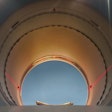

Absolute dose difference of 4D dose distributions considering ground truth motion versus reconstructed motion from either the PCA model (top) or the 2D translation model (bottom) prediction for three fields (the arrows indicate the field direction). All images courtesy of Ye Zhang.

Absolute dose difference of 4D dose distributions considering ground truth motion versus reconstructed motion from either the PCA model (top) or the 2D translation model (bottom) prediction for three fields (the arrows indicate the field direction). All images courtesy of Ye Zhang.At the PSI, the newest proton therapy gantry (Gantry2) is equipped with a beam's eye view (BEV) imaging system that can acquire 2D x-ray fluoroscopy images during proton therapy. But what's really needed is information regarding the 3D deformable motion throughout the whole target region. To achieve this, the PSI team has proposed a method for extracting 3D motion from surrogate motion detected using the BEV system (Physics in Medicine and Biology, 2013 November 21, Vol. 58:24, pp. 8621-8645).

To further investigate the feasibility of motion tracking for scanned proton beam therapy, the PSI team examined the effect of motion prediction errors on the resulting 4D dose distributions. For all subjects, they calculated 4D dose distributions (for a single field and using Gantry2's scanning parameters) using both the ground-truth motion and predicted motion. Predictions were performed using both the PCA model, where full 3D motion is reconstructed, and a translation model, in which every point in the liver is assigned the same motion vector of the fiducials.

Comparing absolute dose differences between ground truth-based and prediction-based plans (using fiducial markers) showed that motion predictions from the translation-only scenario were poor, with maximum dose differences of more than 50%. Plans based on PCA-predicted motion, on the other hand, were similar to those based on ground-truth motion. Here, absolute dose differences of more than 5% occurred in only 3.61% (median) or 15.13% (maximum) of dose calculation points in the irradiated volume. Similar results were seen when tracking diaphragm motion.